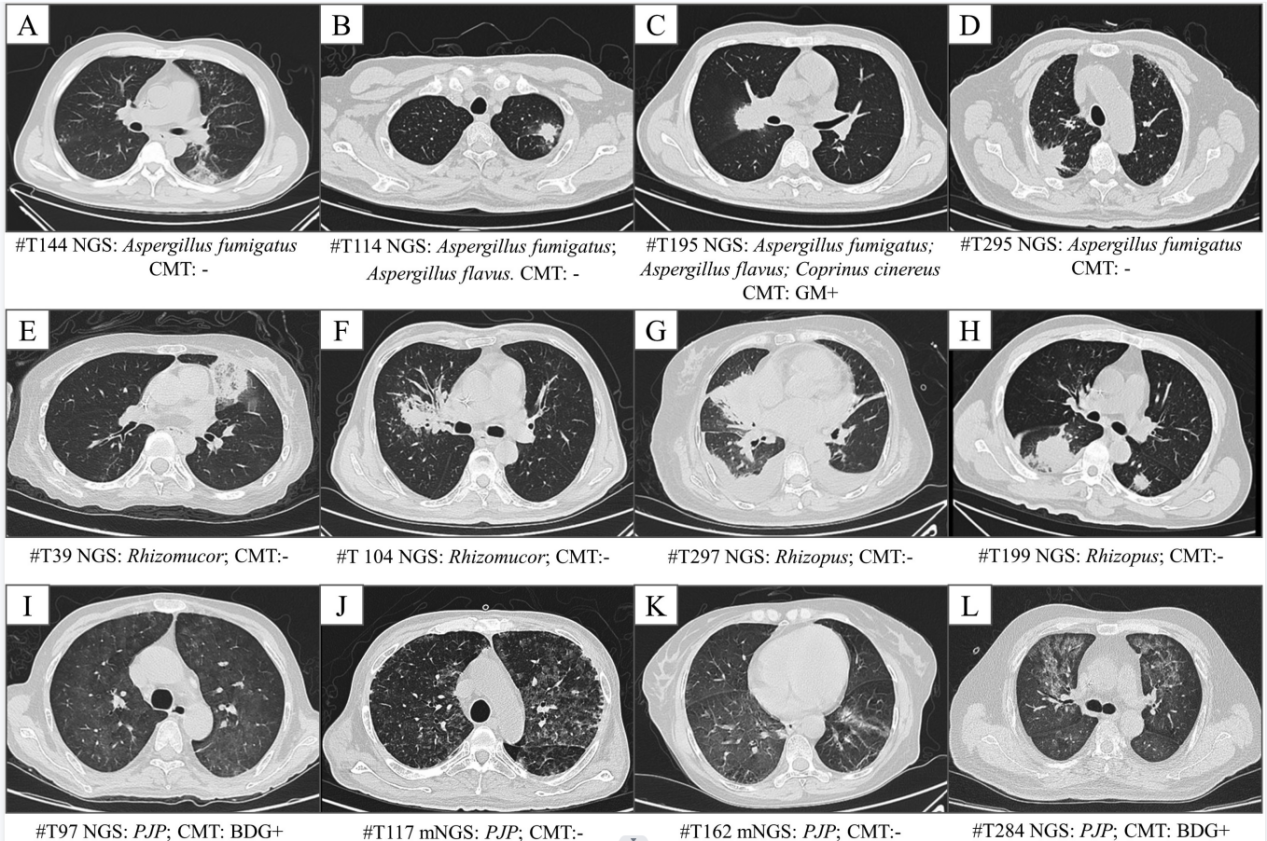

隨后,研究者對血液樣本病原mNGS檢測在疑似肺部真菌感染患者中的診斷價值進(jìn)行分析。結(jié)果顯示,曲霉、毛霉、肺孢子菌這三種血液病患者肺部感染最常見的真菌病原,檢出率分別為14.2%、8.1%和5.0%。其中粒缺患者曲霉檢出率高于非粒缺患者,檢出曲霉的23名患者中,傳統(tǒng)微生物學(xué)檢測僅檢出10名患者。對檢出真菌的46名患者,臨床醫(yī)生對其半數(shù)以上進(jìn)行了藥物調(diào)整,優(yōu)化了抗真菌感染治療策略。